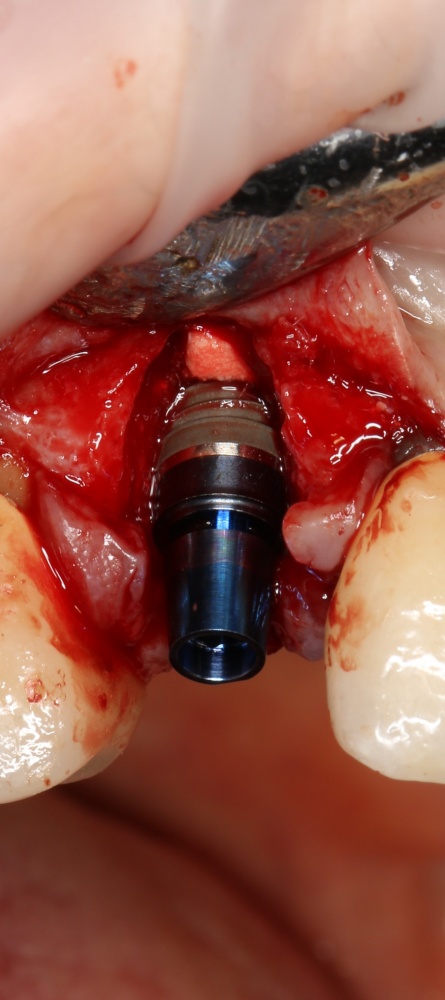

Рекомендации по установке имплантов. Для всех. Часть V.